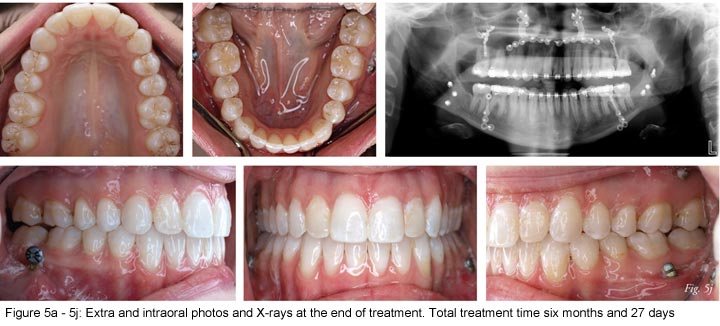

Recently, at the University of Connecticut and at the Instituto de Ciencias de la Salud the surgery first technique has been simplified.24-26 Instead of placing a passive wire at the time of surgery, a NiTi aligning wire is placed in both arches just before the surgical procedure. By doing so, it eliminated the complicated task of bending a passive rectangular stainless steel wire to a malaligned arch. In addition, the window of the RAP might be maximized as the tooth movement is occurring immediately after surgery. The technique has been applied primarily to the treatment of Class III malocclusions with significant reduction in treatment times (Figures 1-5). This technique appears to be promising as patients are greatly satisfied with the short treatment times and the immediate "makeover," without the accentuation of the deformity often observed after the presurgical decompensation phase.